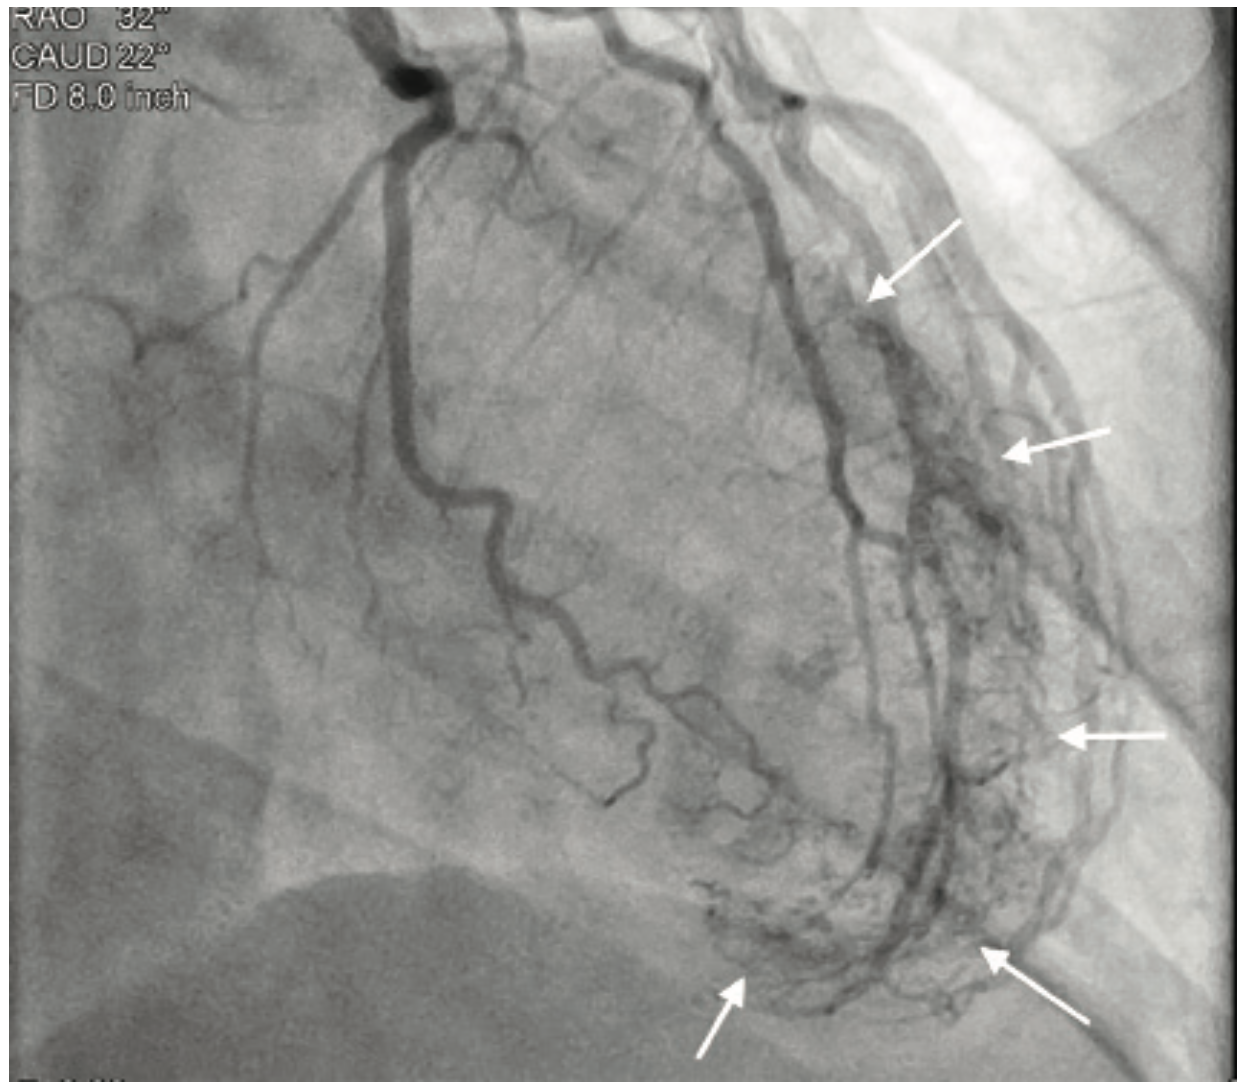

Video 1. Caudal view demonstrating ventricular blushing from the coronary angiogram.

Coronary angiography revealed no significant coronary artery disease, with only a minor lesion in the proximal right coronary artery. Left ventriculography was performed using a power injector. The patient had an approximate ejection fraction of 60% and there was no angiographic evidence of regurgitation. Following coronary angiography, the patient underwent an echocardiogram to further investigate the systolic murmur. No significant findings were discovered; however, a bicuspid aortic valve was noted, a congenital anomaly occurring in 1-2% of patients.1 Although the coronary arteries showed no significant disease, there was significant capillary blushing during injections of the left coronaries. A closer review of the images showed the blushing originating from a diagonal branch of the left anterior descending artery with a direct connection to the interior of the left ventricle, effectively providing a simultaneous coronary angiogram and ventriculogram.

Thebesian veins are generally found incidentally during coronary angiography2 and are the remnant of nutrient supply pathways in the embryonic heart3. In this case, the vessels provide a direct connection from the epicardial coronary arteries into the left ventricle. Although Thebesian veins are a rare angiographic find and the clinical effects are not entirely clear, they can make for very dramatic and interesting angiography.